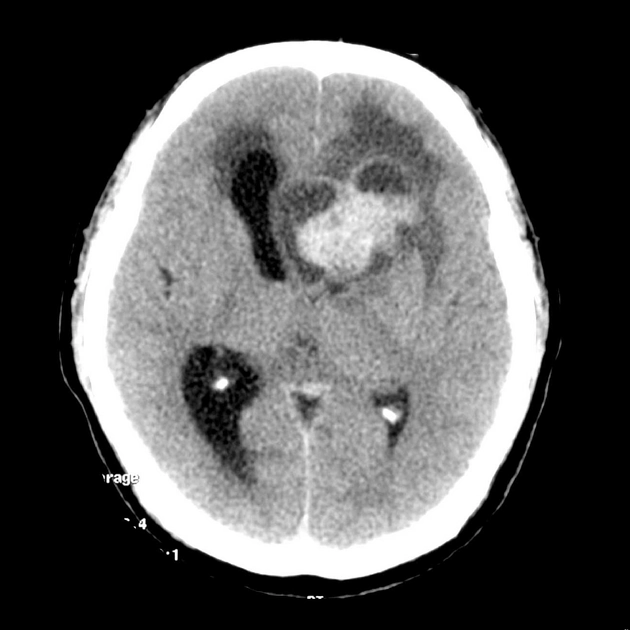

• Xuất huyết trong nhu mô não tự phát không do chấn thương (Spontaneous Nontraumatic Intracranial Hemorrhage - pICH)

• Xuất huyết não do tăng huyết áp (Hypertensive Intracerebral Hemorrhage - HICH)